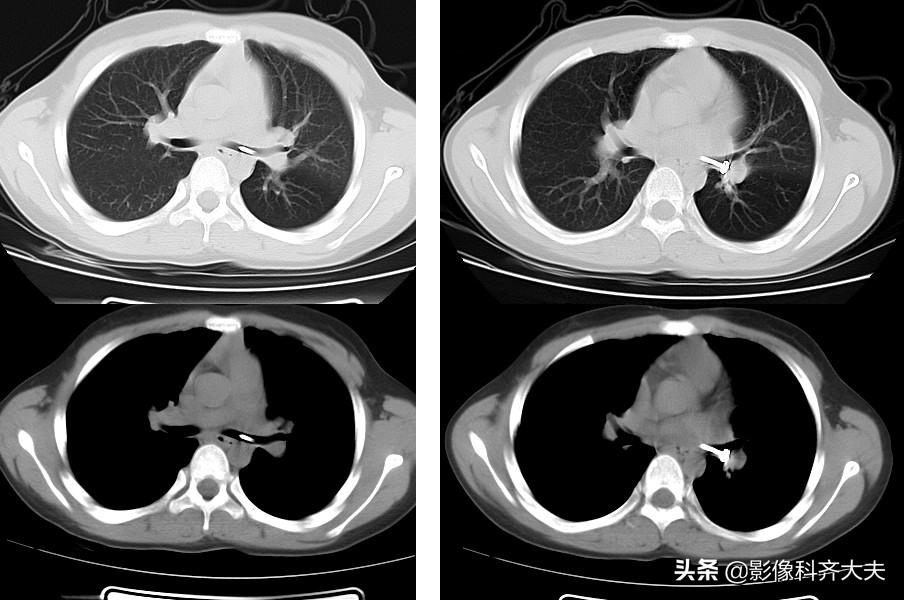

病例5、病史:女,1岁,咳喘12天无好转

轴位图

轴位显示左肺明显肺气肿,左侧支气管似有异常。为进一步明确诊断,遂进行CT三维重建

进行MPR(多平面重组)冠状位重建,清晰显示左侧左侧支气管有异物。

最小密度投影重建对于异物的显示更加清晰,红色箭头所示。